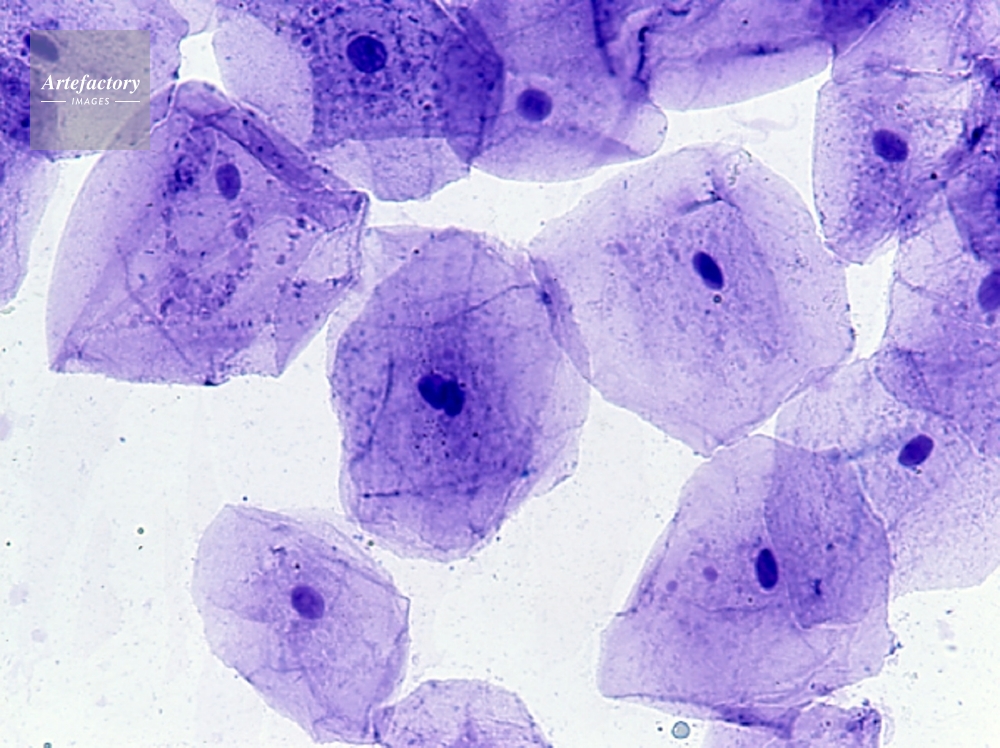

| 作品タイトル | ホオの粘膜(ヒト) | モデルリリース | なし | |

| キャプション | メチレンブルー染色、長辺55mmの場合 200倍 | 制限事項 | こちらはポジのみの画像です。貸出中につきご提供できない場合はご了承ください。 | |